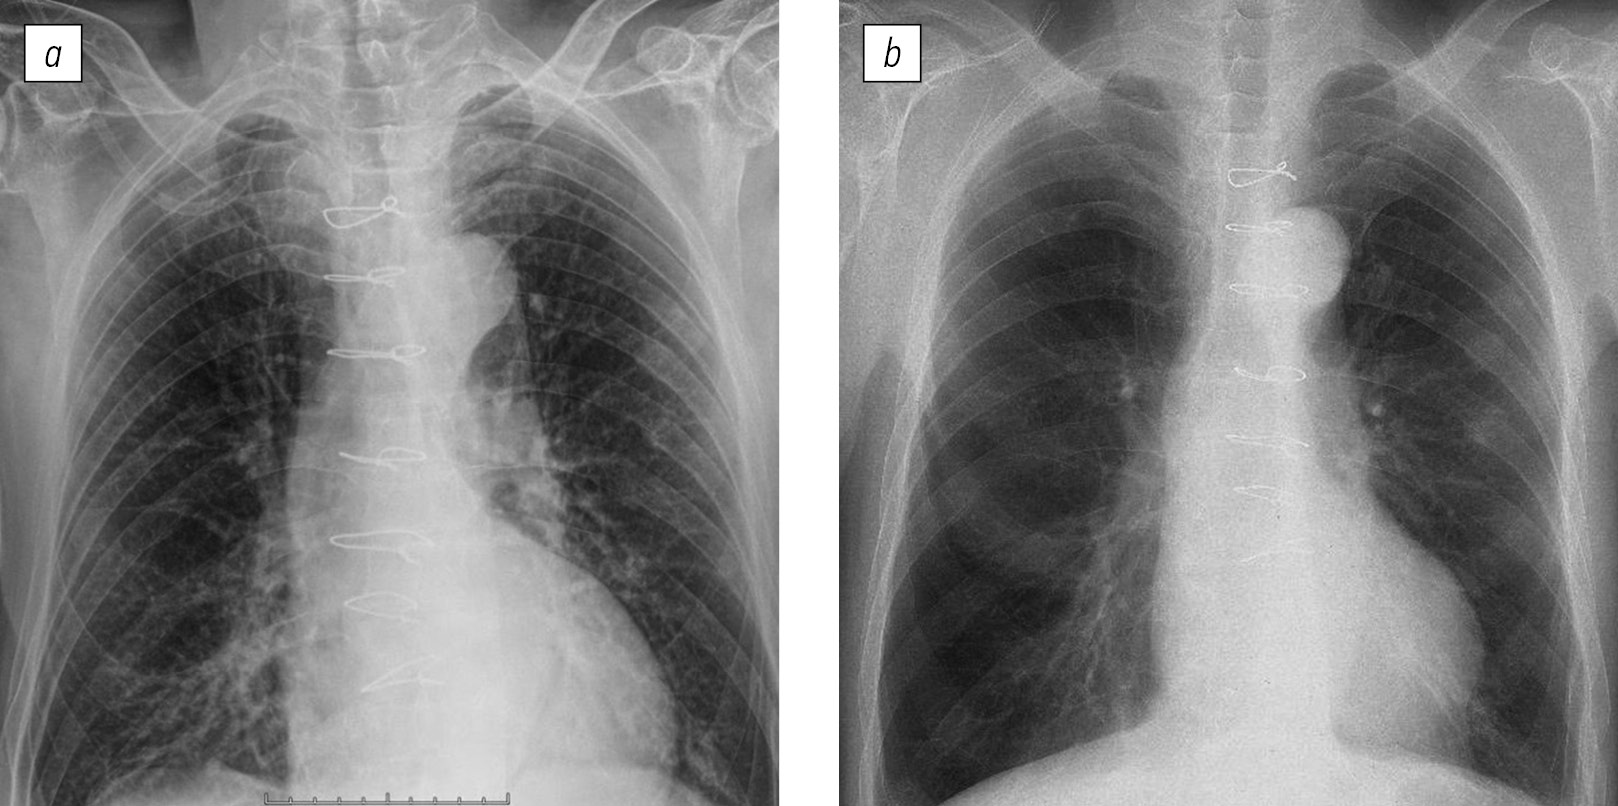

Рис. 3. Рентгенограмма органов грудной клетки в прямой проекции пациента С (36 лет, рассчитанная начальная концентрация карбоксигемоглобина в крови 64%, тяжелая степень интоксикации), выполненная на 1-е сутки после воздействия химического фактора пожара. Патологических изменений не выявлено.

Fig. 3. X-ray of the chest organs in the direct projection of patient С (36 years old, the calculated initial concentration of carboxyhemoglobin in the blood is 64%, corresponds to a severe degree of intoxication), performed on day 1 after exposure to the chemical factor of fire. No pathological changes were detected.

Длительность госпитализации пациентов с интоксикацией тяжелой степени составила 4 [4; 6] сут, средней степени — 4 [2; 5, 7] сут, легкой степени — 3 [2; 5, 5] сут. Значимых различий по длительности госпитализации пациентов в зависимости от степени тяжести состояния, определенного по рассчитанной начальной концентрации карбоксигемоглобина в крови, выявлено не было. Доля пациентов, у которых выявили интерстициальные изменения в легких, значимо не зависела от степени тяжести состояния (табл. 1). Так, у пациентов с тяжелой (рис. 1) и легкой (рис. 2) степенью состояния определены сходные интерстициальные изменения в тканях легких на рентгенограммах органов грудной клетки. В то же время у 37 ± 15% пациентов в тяжелом состоянии интерстициальных изменений в тканях легких при анализе рентгенограмм органов грудной клетки выявлено не было (рис. 3).